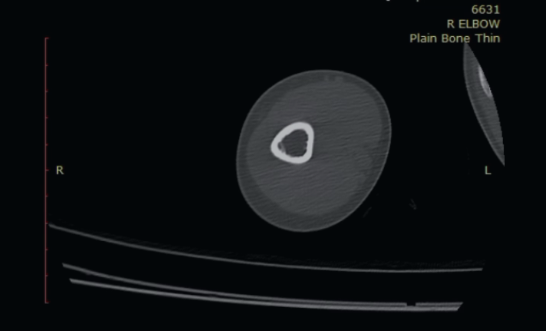

Body imaging is central to modern medicine—from early diagnosis to guiding treatment and follow-up. As our field continues to evolve, our mission is to embrace innovation responsibly, apply it ethically, and translate it into meaningful clinical impact.